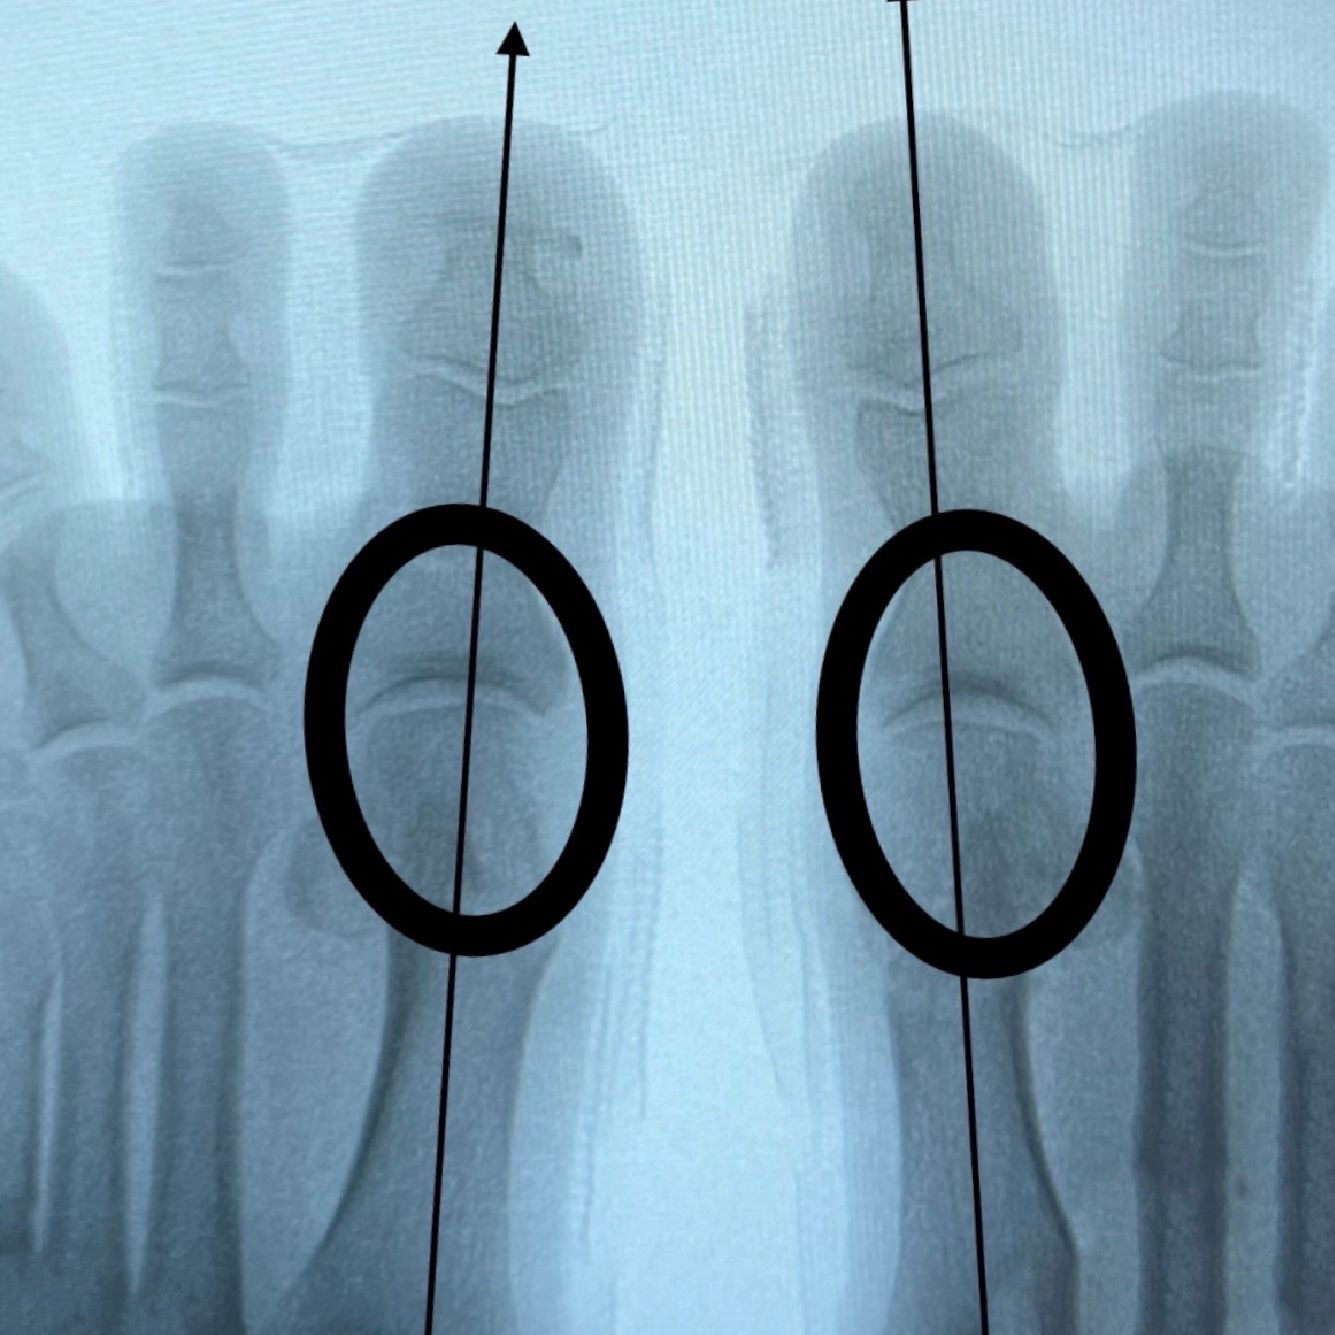

Золотым стандартом исследования при планировании хирургического лечения является рентгенография стопы в прямой и боковой проекциях с нагрузкой.

Угол отклонения большого пальца стопы более 15 градусов является диагностическим критерием патологического вальгусного отклонения. Так же в качестве дополнительных диагностических методов возможно применять МРТ, КТ, плантографию, биомеханический анализ походки и давления.

Миниинвазивная хирургия стопы отличается от классической хирургии стопы тем, что переломы костей, истирание костных выступов, изменения сухожильно - связочного аппарата стопы и ее выравнивание в правильном положении, производят специальными миниинвазивными скальпелями и фрезами через небольшие (3 - 5 мм) разрезы кожи под контролем рентгена.